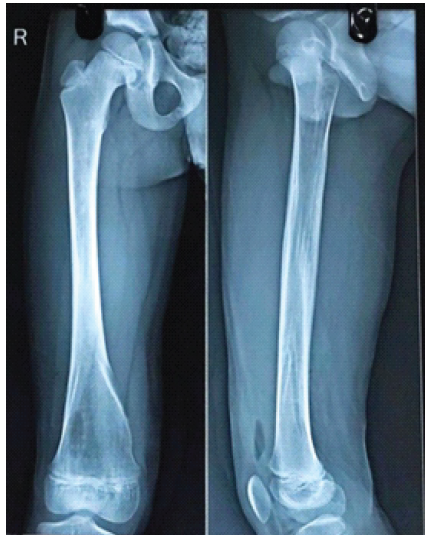

Post-operatively, patients were followed for 6 months with evaluations at 6, 12, and 24 weeks. Partial weight bearing was started at 6 weeks and gradually increased to full weight bearing once radiographic evidence of fracture union was observed on anteroposterior and lateral X-rays. During follow-up, patients were assessed for the time to fracture union, the occurrence of complications, such as superficial or deep infections, implant prominence or migration, fracture angulation, loss of reduction, fracture collapse, limb shortening, and range of motion. In addition, at the past follow-up, an orthoroentgenogram (scanogram) was performed to check whether there was limb length discrepancy (LLD). Pain, malalignment, LLD, and complications were reported and classified according to Flynn’s criteria. Ethical clearance was taken from the institute. In the image, Fig. 1 is showing mid 1/3rd shaft of femur fracture. Fig. 2 & 3 is showing immediate post-operative X-ray. Fig. 4 shows 2 years of follow-up, and Fig. 5 shows the X-ray after hardware extraction.

Figure 5: After implant removal.